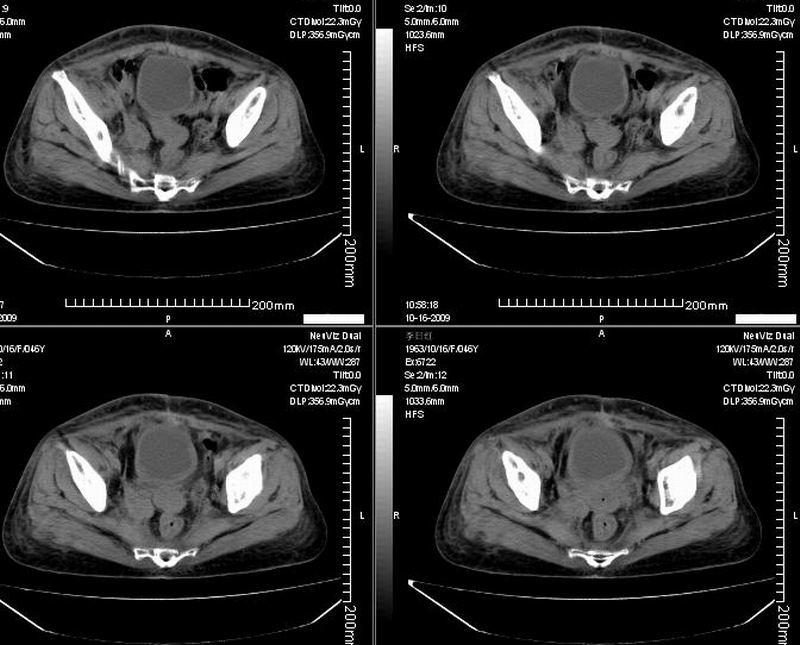

女:46y:一年前宫颈癌术后,现右下腹抚及肿块。

考虑宫颈癌术后复发周边侵犯/右中下腹及双侧腹股沟淋巴结转移。

考虑宫颈癌术后复发周边侵犯并右中下腹转移灶及双侧腹股沟淋巴结转移。